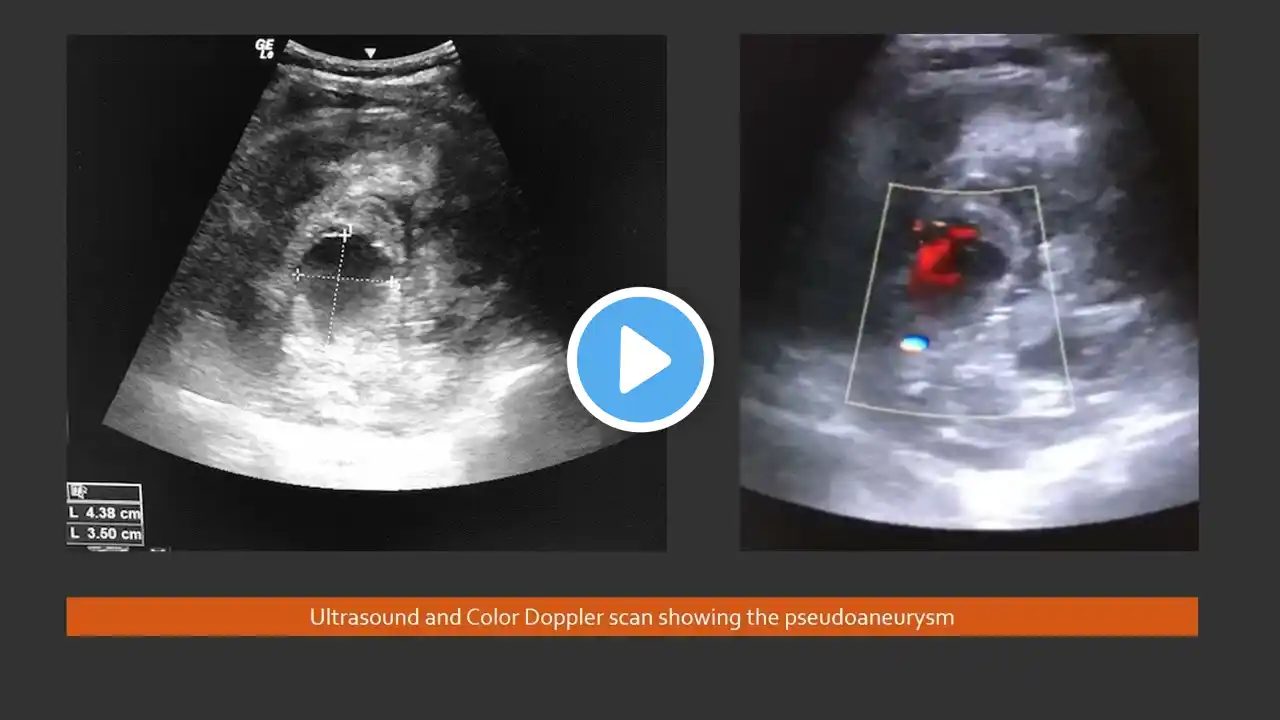

Bronchial and systemic artery glue embolization for massive recurrent hemoptysis using nBCA (n-butyl cyanoacrylate) in a young female patient with damaged right lung | AIIMS Patna | Interventional Radiology